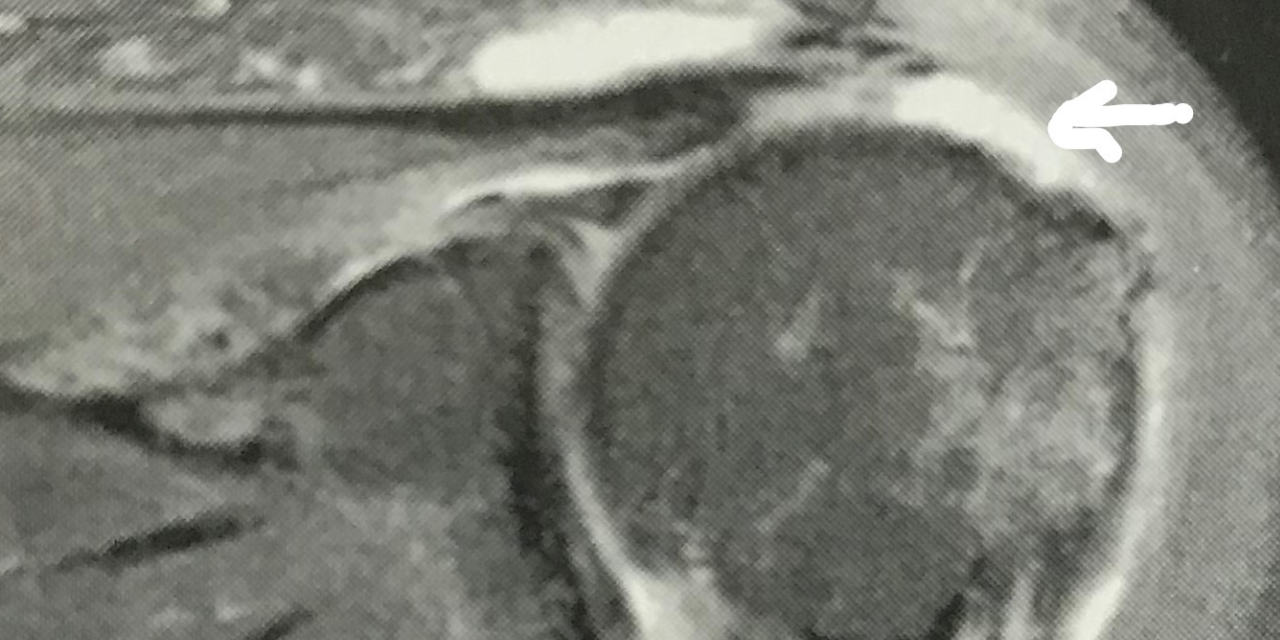

On MRI the appearance of the inferior joint capsule is one of thickening and a generally indistinct appearance. The margins of the capsule may appear fuzzy. Figure 1, a sagittal T-2 weighted image, demonstrates the normally well-defined non-thickened inferior joint capsule (joint fluid appears as hyperintense white signal extending down along the joint to the capsule). Note the well-defined inferior border (arrow). Contrast that image with figure 2, which shows the inferior capsule as thickened, with an increase in signal intensity on this STIR weighted sagittal image. Figure 3 demonstrates adhesive capsulitis that is concurrent with a torn rotator cuff tendon. The arrow indicates the gap left in the tendon that is now filled in with high signal intensity fluid on this STIR sagittal image. There has been retraction of the musculotendinous junction. The inferior joint capsule is poorly defined, intermediate in signal intensity, and grossly thickened.